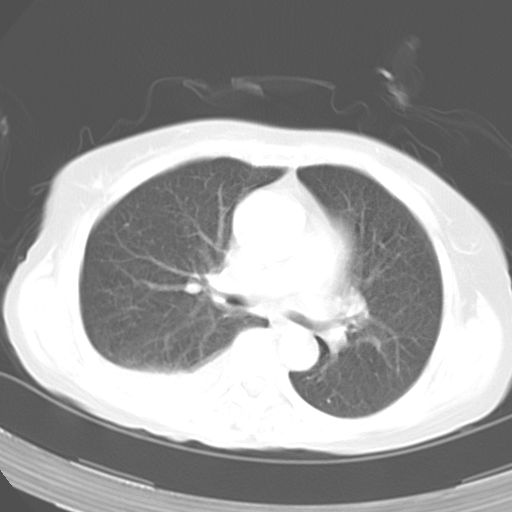

以下是引用dyqct在2006-12-7 21:08:00的发言:[br]考虑:1、肝内外胆管多发性结石伴肝左叶外侧段肝萎缩;[br] 2、右膈下多发脓肿;[br] 3、右侧少量胸腔积液、斜裂积液;[br] 4、左肾囊肿。

以下是引用jiazh在2006-12-7 20:37:00的发言:[br]肝脏周围半狐形低密度影,肝脏表面受压推移,考虑膈下脓肿可能性大;2、右侧胸腔积液

以下是引用拾荒者在2006-12-7 21:44:00的发言:[br]肝内外胆管多发结石,右膈下多发脓肿,右胸膜腔及叶间裂积液,左肾囊肿。[br] [br]